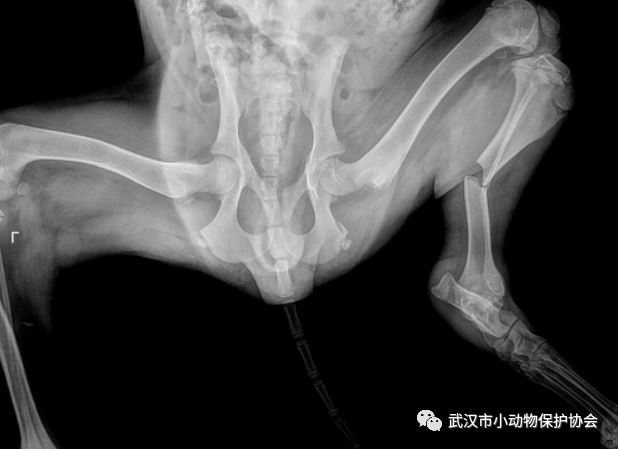

救助经过:发现人与协会联系,在发现小区旁边的墙角处有只狗狗疑似受伤了不能动,一直缩在墙角不吃不喝。到达现场后成功救助并送至动物医院,经检查为车祸伤导致的骨盆骨折以及睾丸损伤,后续将手术修复。

长利 的双侧骨折修复,绝育手术和住院费用共计3200元。